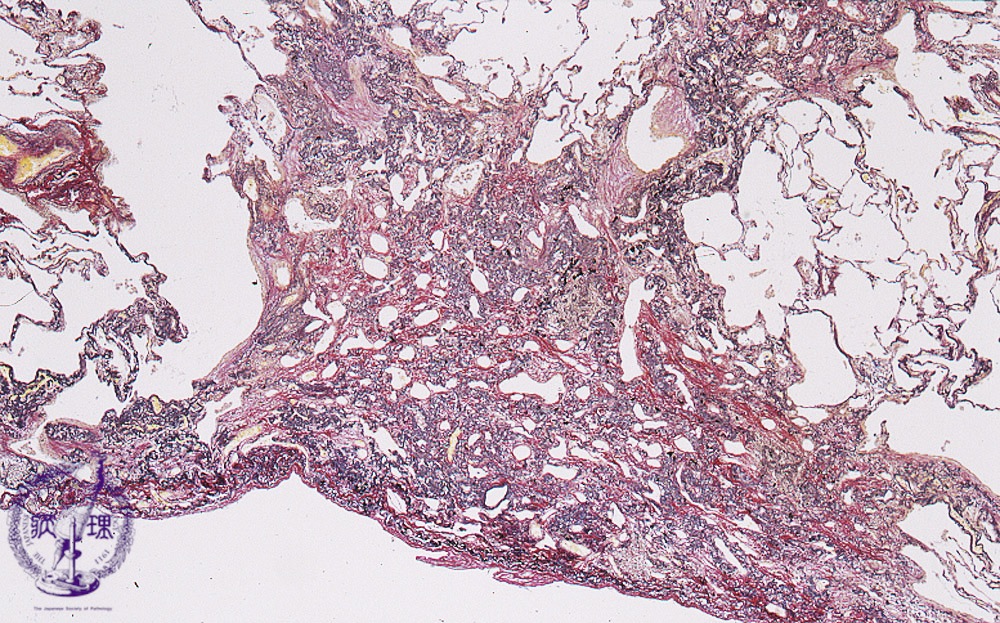

Microscopic view (HE stain, low power view): Long-standing collapse induces fibrosis (collapse fibrosis).